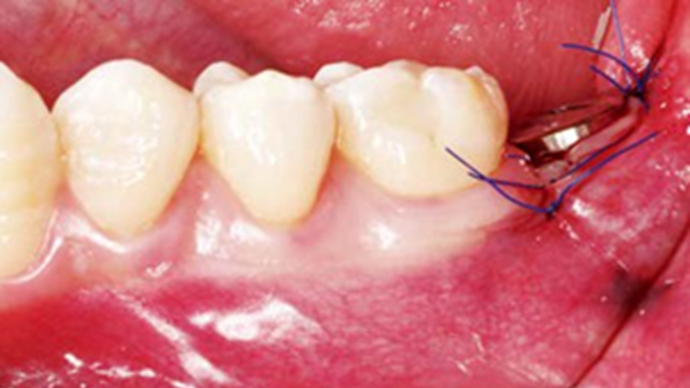

Clinical case: Bone filling into the bottom of deepest thread at 8.0mm AnyRidge fixture

- Courtesy of Dr. Kwang Bum Park -

AnyRidge, Knifethread ,extraction socket, ,initial stability ,Allograft, ,osseointegratio ,Dr. Kwang Bum Park, , Mandibular, Single replacement, AnyRidge, Mega-oss,

Implant system-AnyRidge, Regeneration-Mega-Oss